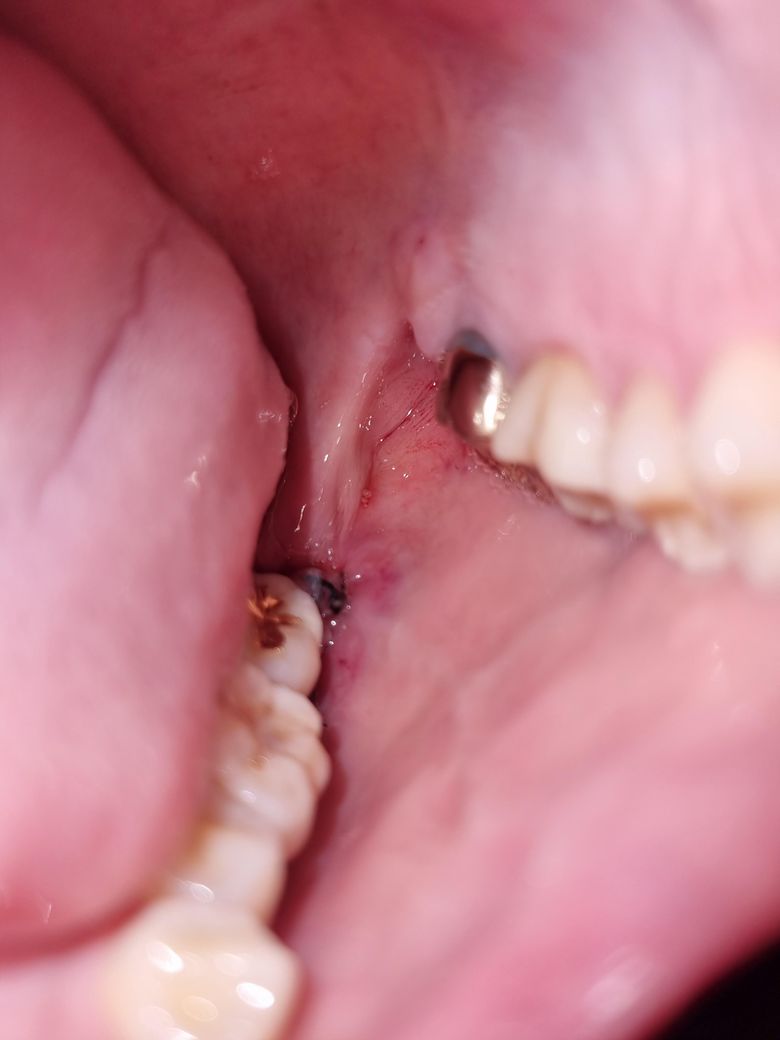

어제 오후에 왼쪽 윗,아래사랑니뽑고 그앞에있는 왼쪽 윗어금니(크라운) 윗부분이 약간회색? 이되었습니다. 저회색부위를 만졌다가 뭐잘못될까봐 일단 만지지는않았고 혀로 만졌을때 크라운이 흔들리지는않습니다. 통증x

• 2번 째 사진

1,2. 발치하면서 옆 치아를 건드려 크라운이 약간 벗겨진 것일 수도 있는데 만약 그랬다면 교합 안맞고 바로 알아차립니다

그보다는 애초에 크라운 변연이 짧아서 치아가 노출되어 있는 상태거나 아니면 잇몸퇴축으로 점차 드러난 것 같습니다

사진에 보이는건 치아 색이 변한게 아니라 나이가 들면서 잇몸이 내려가면서 치아가 노출되서 치아가 보이는겁니다. 단순 발치엿다면 3일정도 지나셧고 지혈도 됫고 통증도 없다면 운동을 하셔도 됩니다.

금리로 씌운 부위의 경계 부위는 착색 등으로 인해서 색이 어두워 보일 수 있습니다.